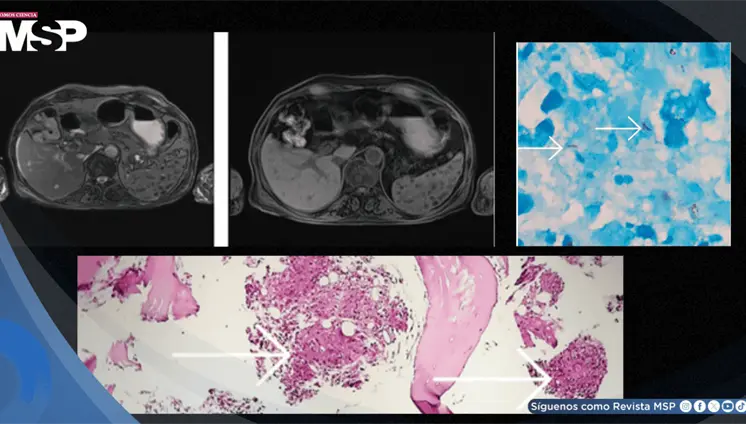

Lo que comenzó como un cuadro frecuente de dolor pélvico y dismenorrea en una mujer, terminó siendo un carcinoma folicular originado en estruma ovárico maligno. La paciente tenía solo 35 años, marcadores tumorales completamente normales y ninguna alteración tiroidea.

La enfermedad avanzó de forma silenciosa durante años, manifestándose únicamente con cambios de personalidad, deterioro cognitivo e incontinencia, lo que llevó a un diagnóstico tardío.

Aunque inicialmente se sospechó un síndrome de Dandy-Walker, los estudios de neuroimagen revelaron el signo del diente molar y un vermis cerebeloso displásico, hallazgos característicos del síndrome de Joubert.